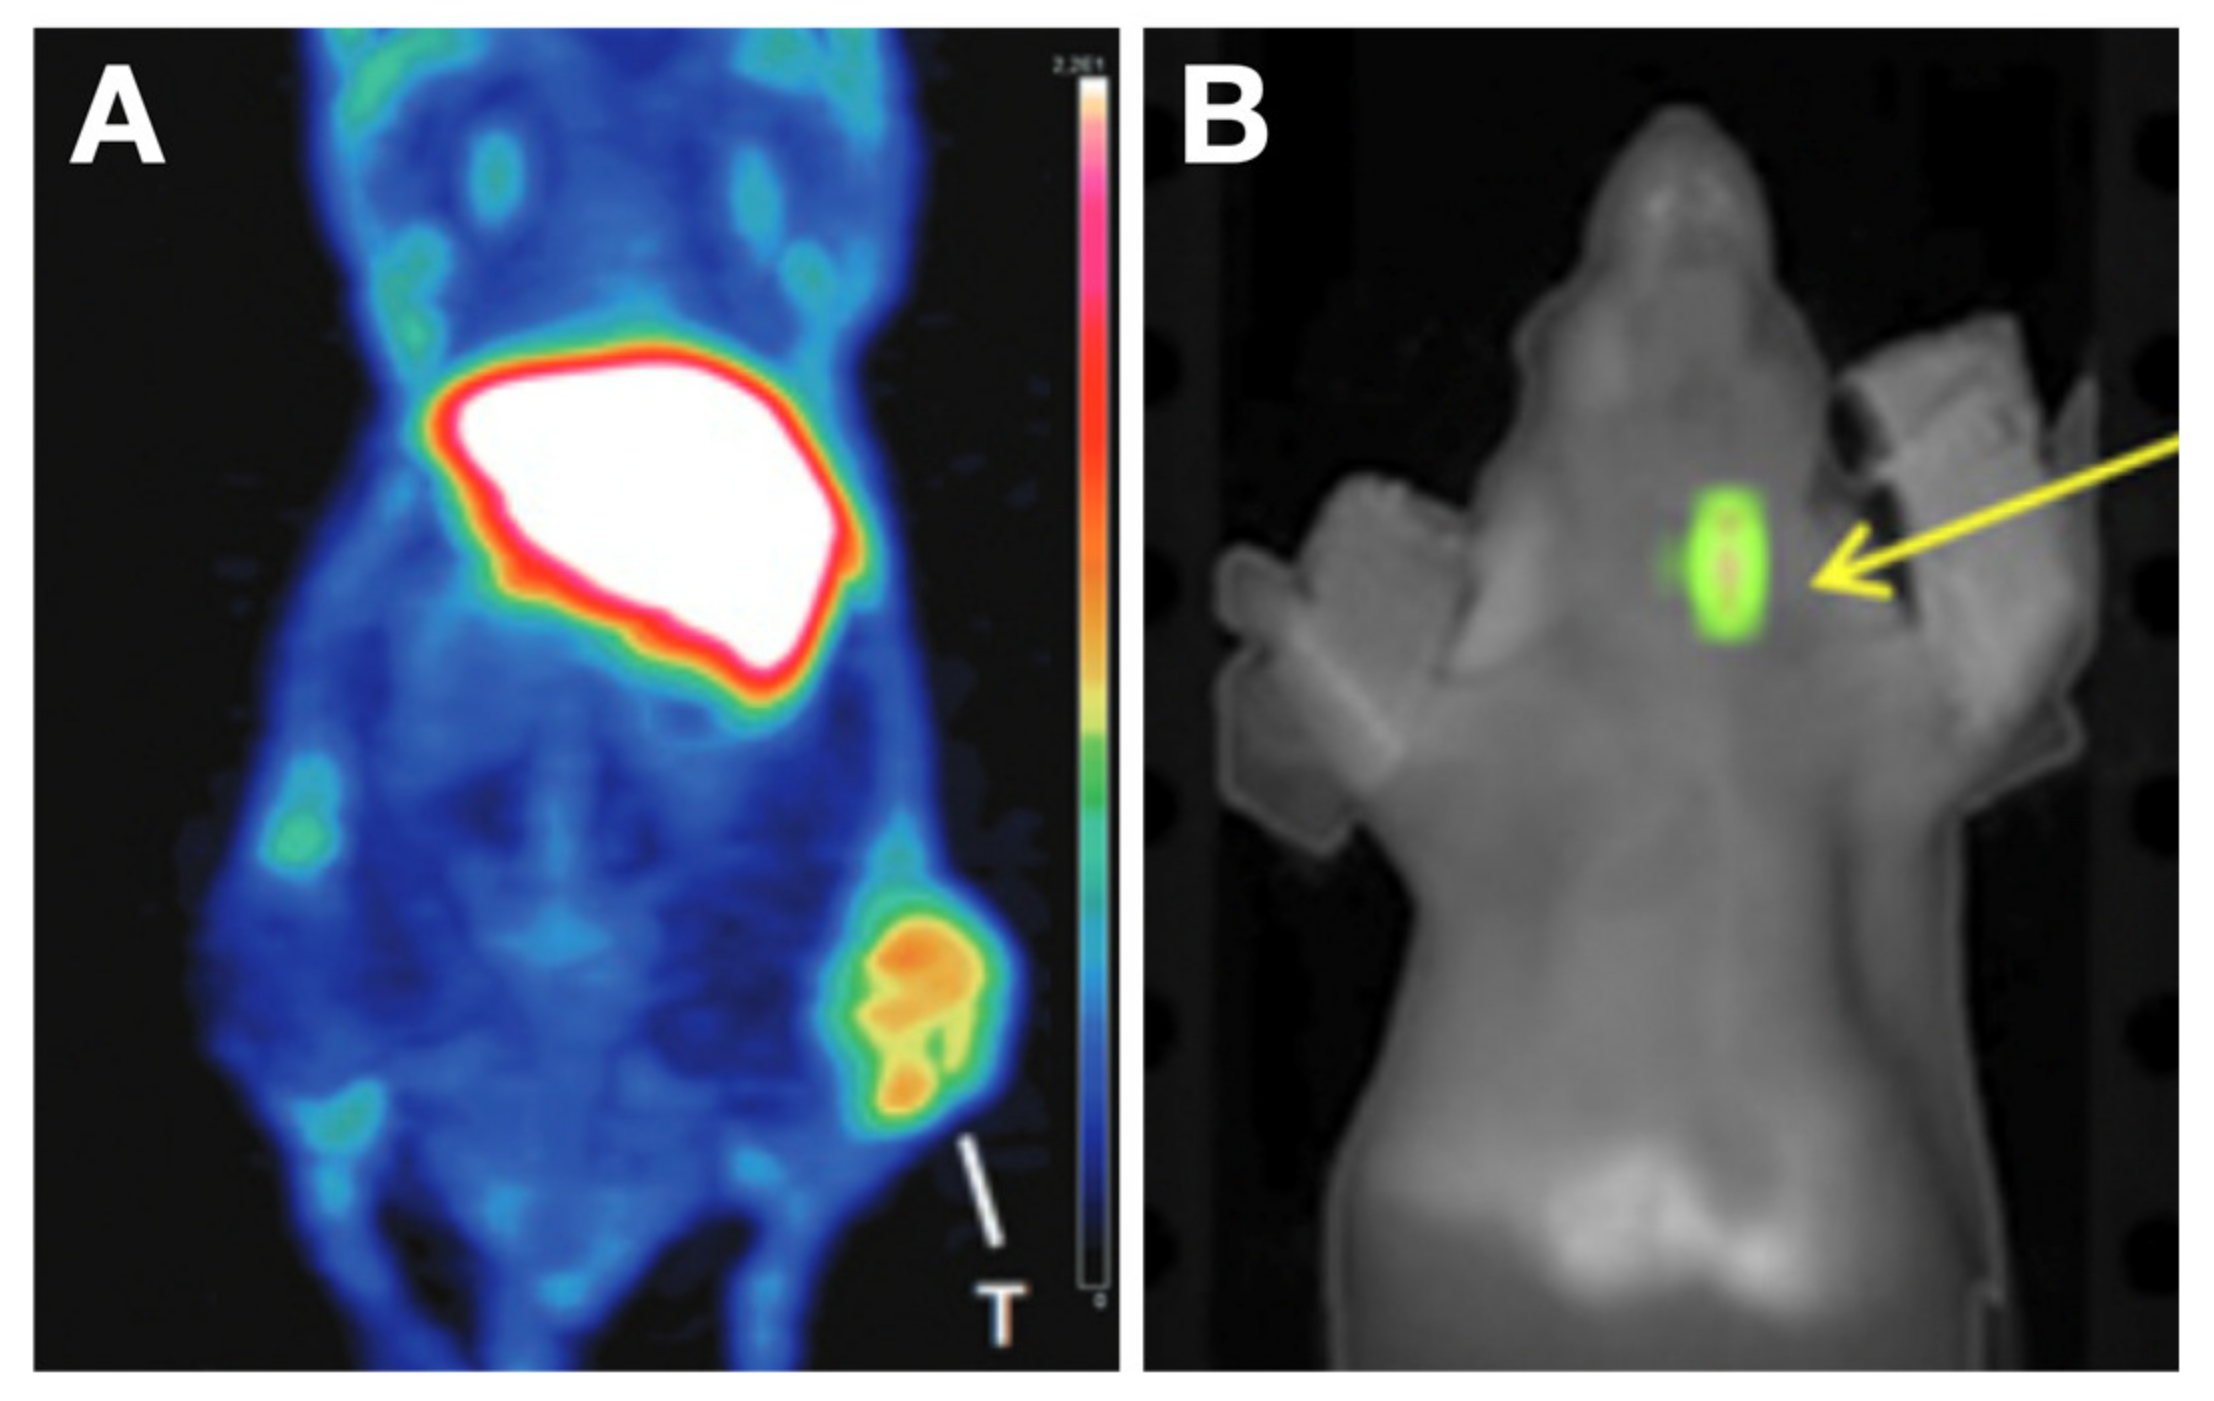

- D’Alessandria, C.; Braesch-Andersen, S.; Bejo, K.; Reder, S.; Blechert, B.; Schwaiger, M.; Bartolazzi, A. Noninvasive In Vivo Imaging and Biologic Characterization of Thyroid Tumors by ImmunoPET Targeting of Galectin-3. Cancer Res. 2016, 76, 3583–3592. [Google Scholar] [CrossRef]

- Rose, F.D.; Braeuer, M.; Braesch-Andersen, S.; Otto, A.M.; Steiger, K.; Reder, S.; Mall, S.; Nekolla, S.; Schwaiger, M.; Weber, W.A.; et al. Galectin-3 Targeting in Thyroid Orthotopic Tumors Opens New Ways to Characterize Thyroid Cancer. J. Nucl. Med. 2019, 60, 770–776. [Google Scholar] [CrossRef]